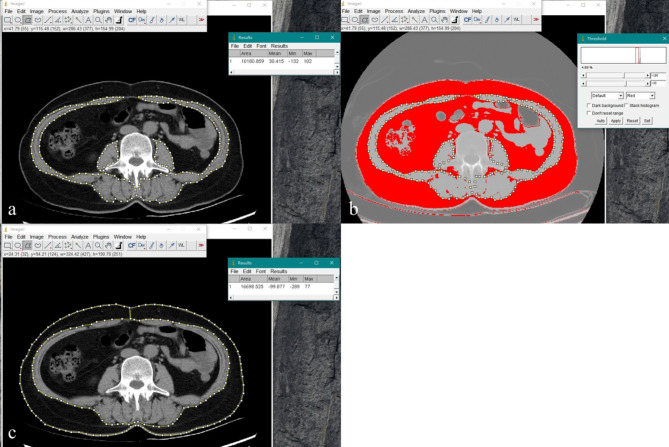

本研究旨在确定肌间脂肪组织(IMAT)或肌内脂肪组织含量(IMAC)对骨骼肌密度(SMD)的影响更大,并探讨其潜在机制。我们招募了292名没有肌肉骨骼系统疾病的住院患者,他们都接受了腹部CT检查。肌肉参数包括骨骼肌面积(SMA)、骨骼肌指数(SMI)、SMD、IMAC和IMAT,以及脂肪参数-腹壁皮下脂肪面积(SFA)和皮下脂肪密度(SFD)由两名肌肉骨骼放射科医生在第三腰椎(L3)水平使用ImageJ软件测量。单因素方差分析采用LSD(组间比较采用卡方检验,p < 0.05)或Dunnett's T3检验(p < 0.05)。研究结果显示,年龄、IMAT和IMAC影响SMD,其中IMAT的影响最为显著。

This study aimed to determine whether intermuscular adipose tissue (IMAT) or intramuscular adipose tissue content (IMAC) has a greater effect on skeletal muscle density (SMD) and to explore the underlying mechanisms. We recruited 292 inpatients without musculoskeletal system disease, all of whom underwent abdominal CT. Muscle parameters, including skeletal muscle area (SMA), skeletal muscle index (SMI), SMD, IMAC, and IMAT, as well as fat parameters-subcutaneous fat area (SFA) and subcutaneous fat density (SFD) in the abdominal wall-were measured by two musculoskeletal radiologists using ImageJ software at the third lumbar vertebra (L3) level. One-way ANOVA with LSD (chi-square test for group comparisons where p > 0.05) or Dunnett's T3 test (p < 0.05) was employed to compare muscle parameters between genders and across age groups. The relationship between SMD and muscle measurements was analyzed using Spearman's correlation coefficient. Multiple regression analysis identified and compared factors influencing SMD. SMD was highly correlated with IMAT and IMAC (p < 0.05), moderately correlated with gender, age, and SFA (p < 0.05). Multiple linear regression analysis indicated that IMAC, IMAT, and age significantly affected SMD (p < 0.05), with the order of influence being IMAT (β = -0.616), IMAC (β = -0.429), and age (β = -0.098). SFA and gender did not significantly affect SMD (p > 0.05). The findings revealed that age, IMAT, and IMAC influence SMD, with IMAT exerting the most significant impact.